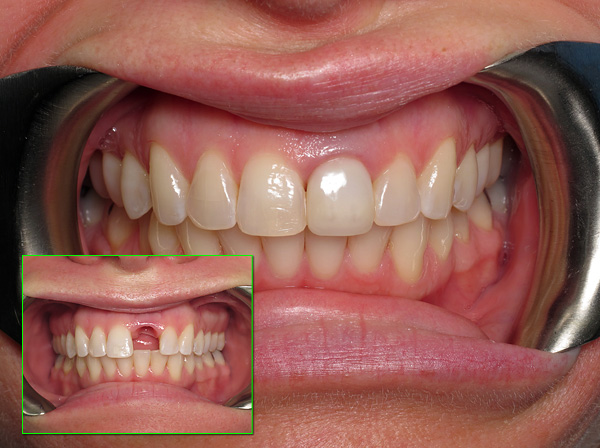

E sotto la foto mostra farfalla protesica (in realtà, questa è una protesi temporanea, tuttavia, molte persone la usano come permanente):